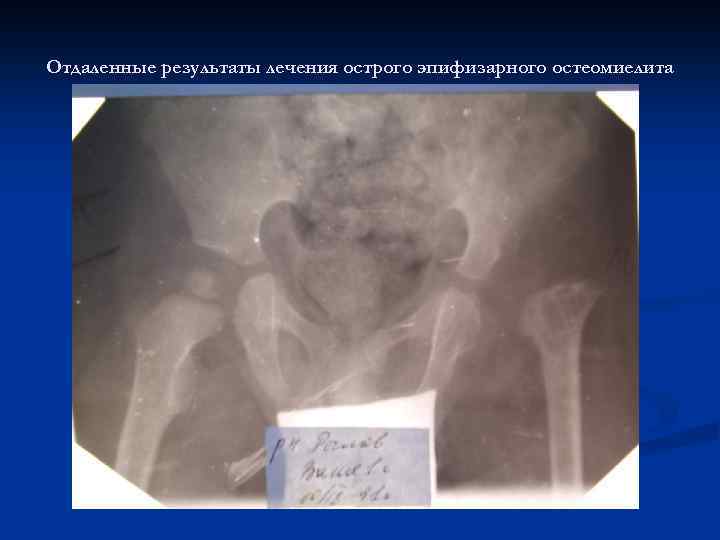

Отдаленные результаты лечения острого эпифизарного остеомиелита